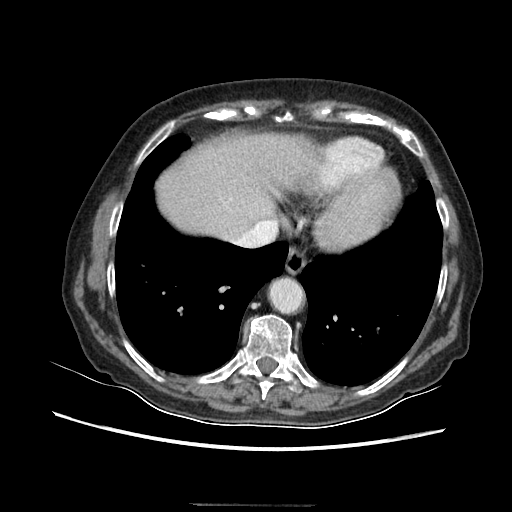

Image Grid

4Γ—3 grid: Rows show different image types (Original NATIVE, Reconstructed NATIVE, Original VENOUS, Generated VENOUS), Columns show windowing techniques (No Window, Lung Window, Mediastinum Window)

Original NATIVE CT scan (input)

Full window (WL 1023.5, WW 4095 β†’ Low βˆ’1024, High +3071)

Original VENOUS CT scan

Generated VENOUS CT scan (A→B translation)